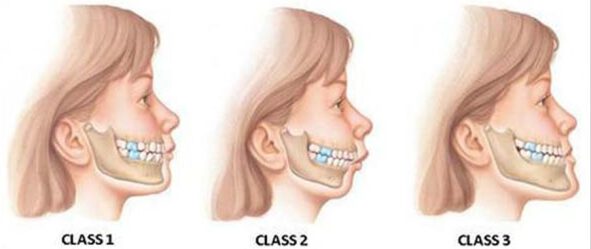

جلو زدگی فک بالا

عقب بودن فک پایین

یا ترکیبی از هردو

به این نوع ناهنجاری در علم ارتودنسی ناهنجاری کلاس دو میگویند.

حالت آندر بایت(Under bite)

آندربایت، اختلال یا ناهنجاری فک و دندان محسوب میشود. فک پایین در این نوع اختلال از حالت نرمال خارج میشود و به سمت جلو میرود. به این حالت در علم ارتودنسی مشکل کلاس سه میگویند.به صورت کلی این ناهنجاری سبب میشود که فک پایین جلوتر از فک بالا قرار گیرد، به عبارتی دندانهای فک پایین، دندانها فک بالا را میپوشانند که به این حالت کراس بایت قدامی میگویند. موارد خفیف این ناهنجاری ممکن است به راحتی و با درمان ارتودنسی ساده بهبود پیدا کند،اما موارد شدید آن باعث بروز مشکلات بسیاری از جمله اختلال در جویدن غذا، اختلال در صحبت کردن، داشتن درد در قسمت مفصل فک و سایش دندانهای جلو میشود. دلیل رایج به وجود آمدن چنین حالتی نیز رشد غیر طبیعی فکها در صورت است. چنین عارضههایی اگر در کودکی به درستی تشخیص داده شوند، به راحتی و در زمان کوتاهتر و با هزینه کمتر با ارتودنسی قابل درمان هستند.

تفاوت کلاس یک ، کلاس دو و کلاس سه

دروضعیت نرمال ، زمانی که دندانها بر روی یکدیگر قرار میگیرند، دندانهای فک بالایی به میزان بسیار کمی دندانهای فک پایین را میپوشانند و یک تا دو میلیمتر هم جلوتر از دندانهای فک پایین هستند. به این حالت کلاس یک میگویند. حال اگر دندانهای فک بالا خیلی بیشتر جلوتر از دندانهای فک پایین باشند به آن ناهنجاری کلاس دو ، و اگر برعکس دندانهای فک پایین جلوتر از دندانهای فک بالا قرار بگیرند به آن ناهنجاری کلاس سه میگویند.

هر دوی این ناهنجاریها میتوانند زیبایی ظاهری فرد را از بین ببرند و سبب بروز مشکلاتی در گفتار، جویدن، بلعیدن و … داشته باشند.